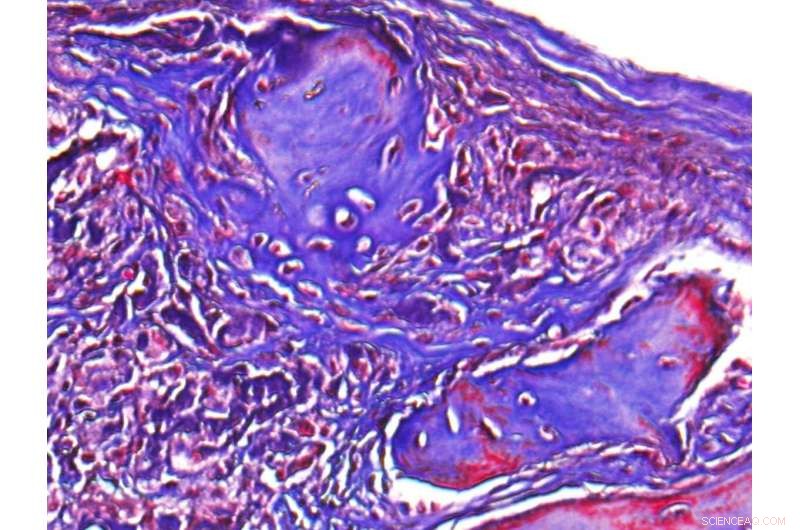

Shown is a microscopic image of regenerated bone in a skull defect in a mouse. Credit: University of California, Los Angeles

The mouse model had a non-healing skull defect, which the researchers injected with their clay-enhanced hydrogel. After six weeks, they found that the model showed significant bone healing through its own naturally occurring stem cell migration and growth.